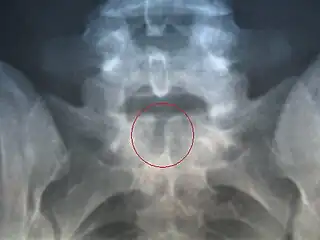

X-ray image of spina bifida occulta in S-1

Many people with this type of spina bifida do not even know they have it, as the condition is asymptomatic in most cases.[19] About 15% of people have spina bifida occulta,[8] and most people are diagnosed incidentally from spinal X-rays. A systematic review of radiographic research studies found no relationship between spina bifida occulta and back pain.[20] More recent studies not included in the review support the negative findings.[21][22][23]